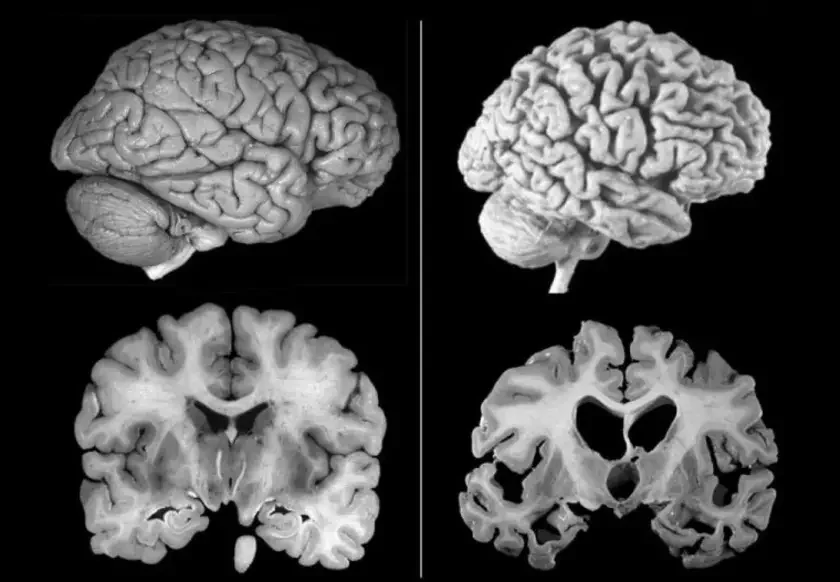

У мозгу пацыентаў былі знойдзены бялкі віруса простага герпесу першага тыпу (ВПГ-1) побач з характэрнымі для захворвання скучанасцямі тау-бялку ў найбольш уразлівых зонах мозгу.

Эксперыменты на лабараторных мадэлях мозгу чалавека паказалі, што вірус герпесу можа ўплываць на ўзровень тау-бялка. Спачатку гэта з’яўляецца ахоўным механізмам, які змяншае гібель нейронаў пасля віруснай інфекцыі. Аднак з цягам часу такая абарона можа прывесці да пашкоджання мозгу.

Тым не менш, дакладныя механізмы, праз якія вірус ВПГ-1 спрыяе развіццю хваробы Альцгеймера, пакуль не вывучаны. Навукоўцы плануюць працягнуць даследаванні, каб распрацаваць метады лячэння, накіраваныя на барацьбу з віруснымі бялкамі або рэгуляцыю імуннага адказу мозгу.